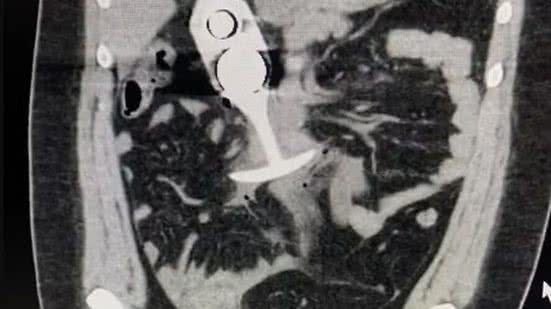

Durante o exame, realizado em uma clínica britânica, o brinquedo foi arrastado da região anal para a cavidade torácica da mulher devido à intensa atração magnética. Após o procedimento, ela começou a gritar de dor, relatando sintomas como náuseas e sensação de desmaio, sendo rapidamente encaminhada para um hospital. O incidente gerou repercussão na internet quando um post circulou com uma imagem e relato sobre a ocorrência, o que despertou preocupação sobre o risco de objetos metálicos durante exames de RM.

A ressonância magnética, que utiliza ímãs com potência entre 0,5 e 3 Tesla, causou uma atração tão forte no metal presente no brinquedo que ele foi movido rapidamente através do corpo da paciente, podendo ter causado danos graves aos órgãos internos. O uso de objetos metálicos é amplamente contraindicado durante esse tipo de exame devido aos riscos de lesões internas.